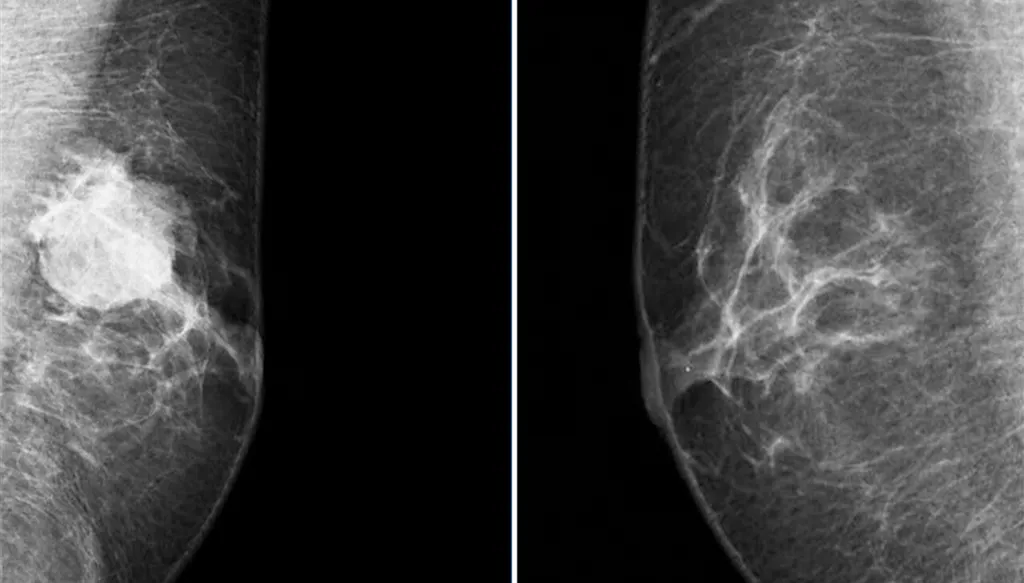

كيف يتم تشخيص المرض؟

غالباً ما يتم اللجوء أولاً إلى صورة صوتية بعد ملاحظة علامة ما، ومن بعدها صورة شعاعية، قبل اللجوء إلى الخزعة. ويمكن اللجوء أيضاً إلى الخزعة في الغدد اللمفاوية.